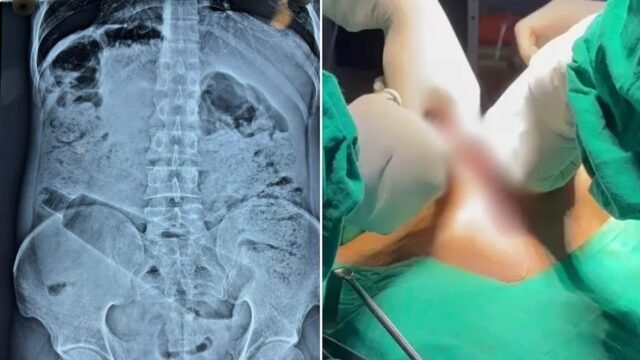

उत्तर प्रदेश के Ambedkar Nagar जिले से एक बेहद हैरान करने वाला मामला सामने आया है, जिसने सभी को चौंका दिया, यहां डॉक्टरों ने एक युवक के पेट से सर्जरी के जरिए प्लास्टिक की बोतल निकालकर उसकी जान बचाई, यह मामला न केवल मेडिकल दृष्टि से जटिल था, बल्कि लोगों के बीच चर्चा का विषय भी बन गया है।

जब दर्द असहनीय हो गया, तो युवक अपने गांव वापस लौट आया और स्थानीय डॉक्टर विपिन वर्मा से संपर्क किया, डॉक्टर ने उसकी स्थिति को देखते हुए तुरंत जांच कराने का निर्णय लिया, अल्ट्रासाउंड और एक्स-रे रिपोर्ट में स्पष्ट रूप से पेट के अंदर एक बोतल दिखाई दी, जिससे स्थिति की गंभीरता का अंदाजा लगाया गया।

इसके बाद डॉक्टरों की टीम ने बिना देर किए सर्जरी करने का फैसला लिया, ऑपरेशन काफी जटिल था, क्योंकि बोतल पेट के अंदर फंसी हुई थी और इससे अंदरूनी अंगों को नुकसान पहुंचने का खतरा था। हालांकि, डॉक्टरों की सूझबूझ और अनुभव के चलते ऑपरेशन सफल रहा और बोतल को सुरक्षित बाहर निकाल लिया गया।